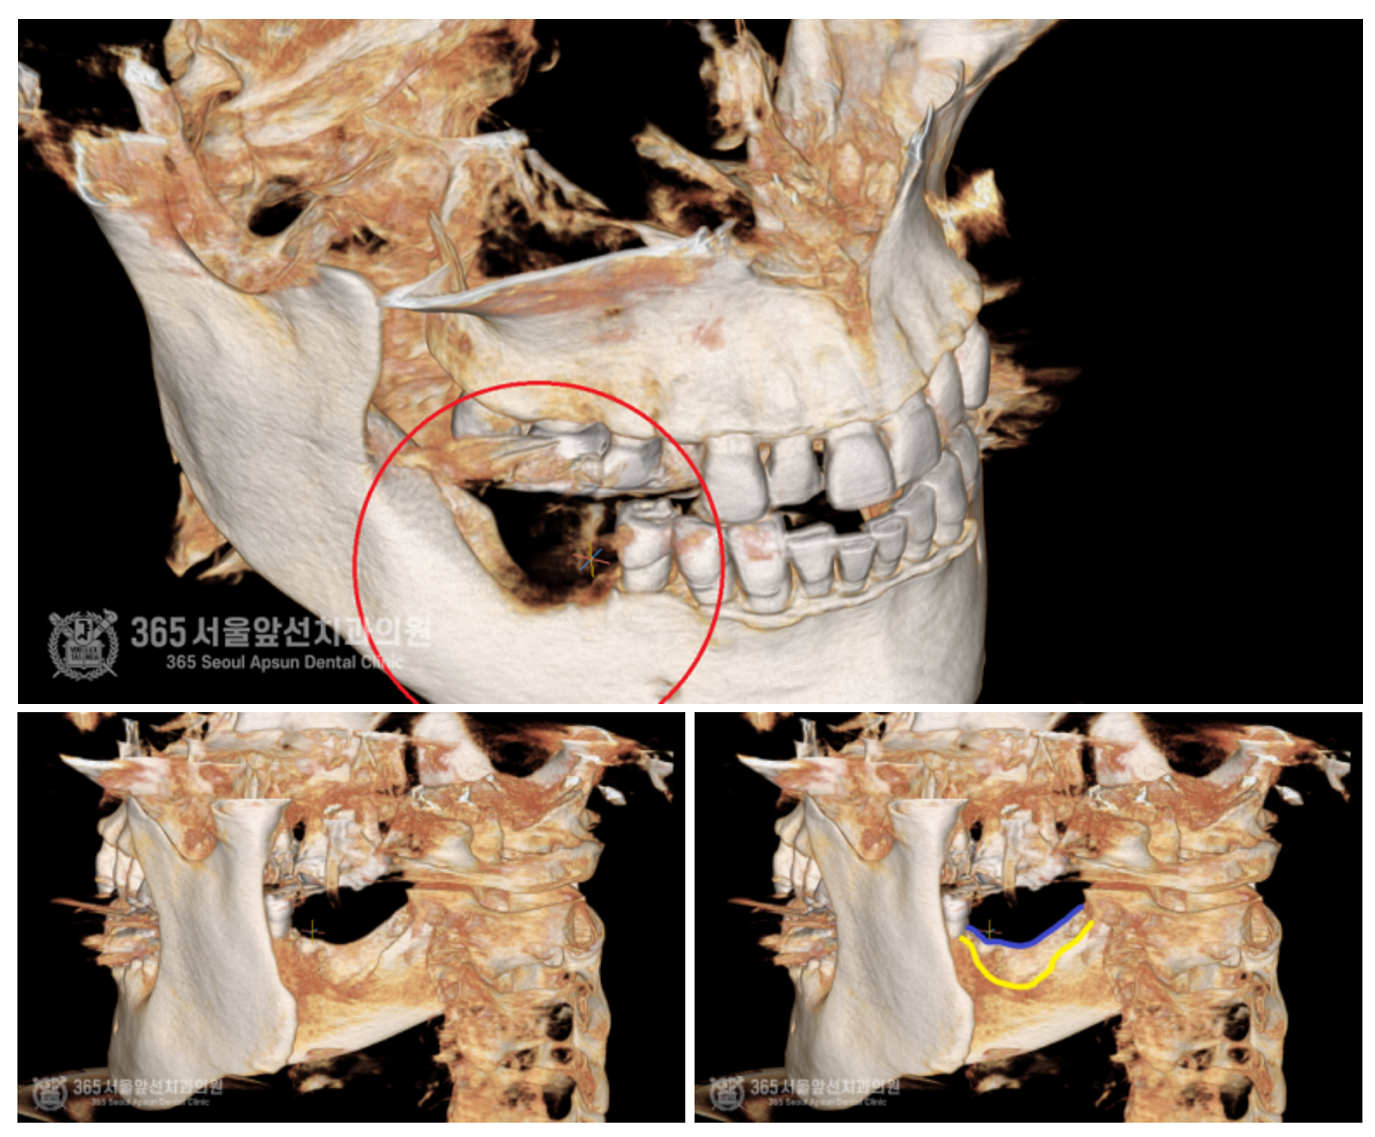

촬영일자:24.05.09 발치가 끝난 후 촬영한 3차원 CT 입니다. 매우 심각하게 매복되어있던 치아들을 발치했던 공간이 크게 함몰되어 있는 것이 관찰됩니다. 추후 임플란트 치료를 위해서 상당량의 뼈이식이 필요함을 알 수 있습니다. 파란색 선: 함몰 부위의 볼쪽 가장자리 선 노란색 선: 함몰 부위의 혀쪽 가장자리 선 뼈손실 부위가 아주 깊게 파여있는 것을 다른 각도에서도 볼 수 있습니다.